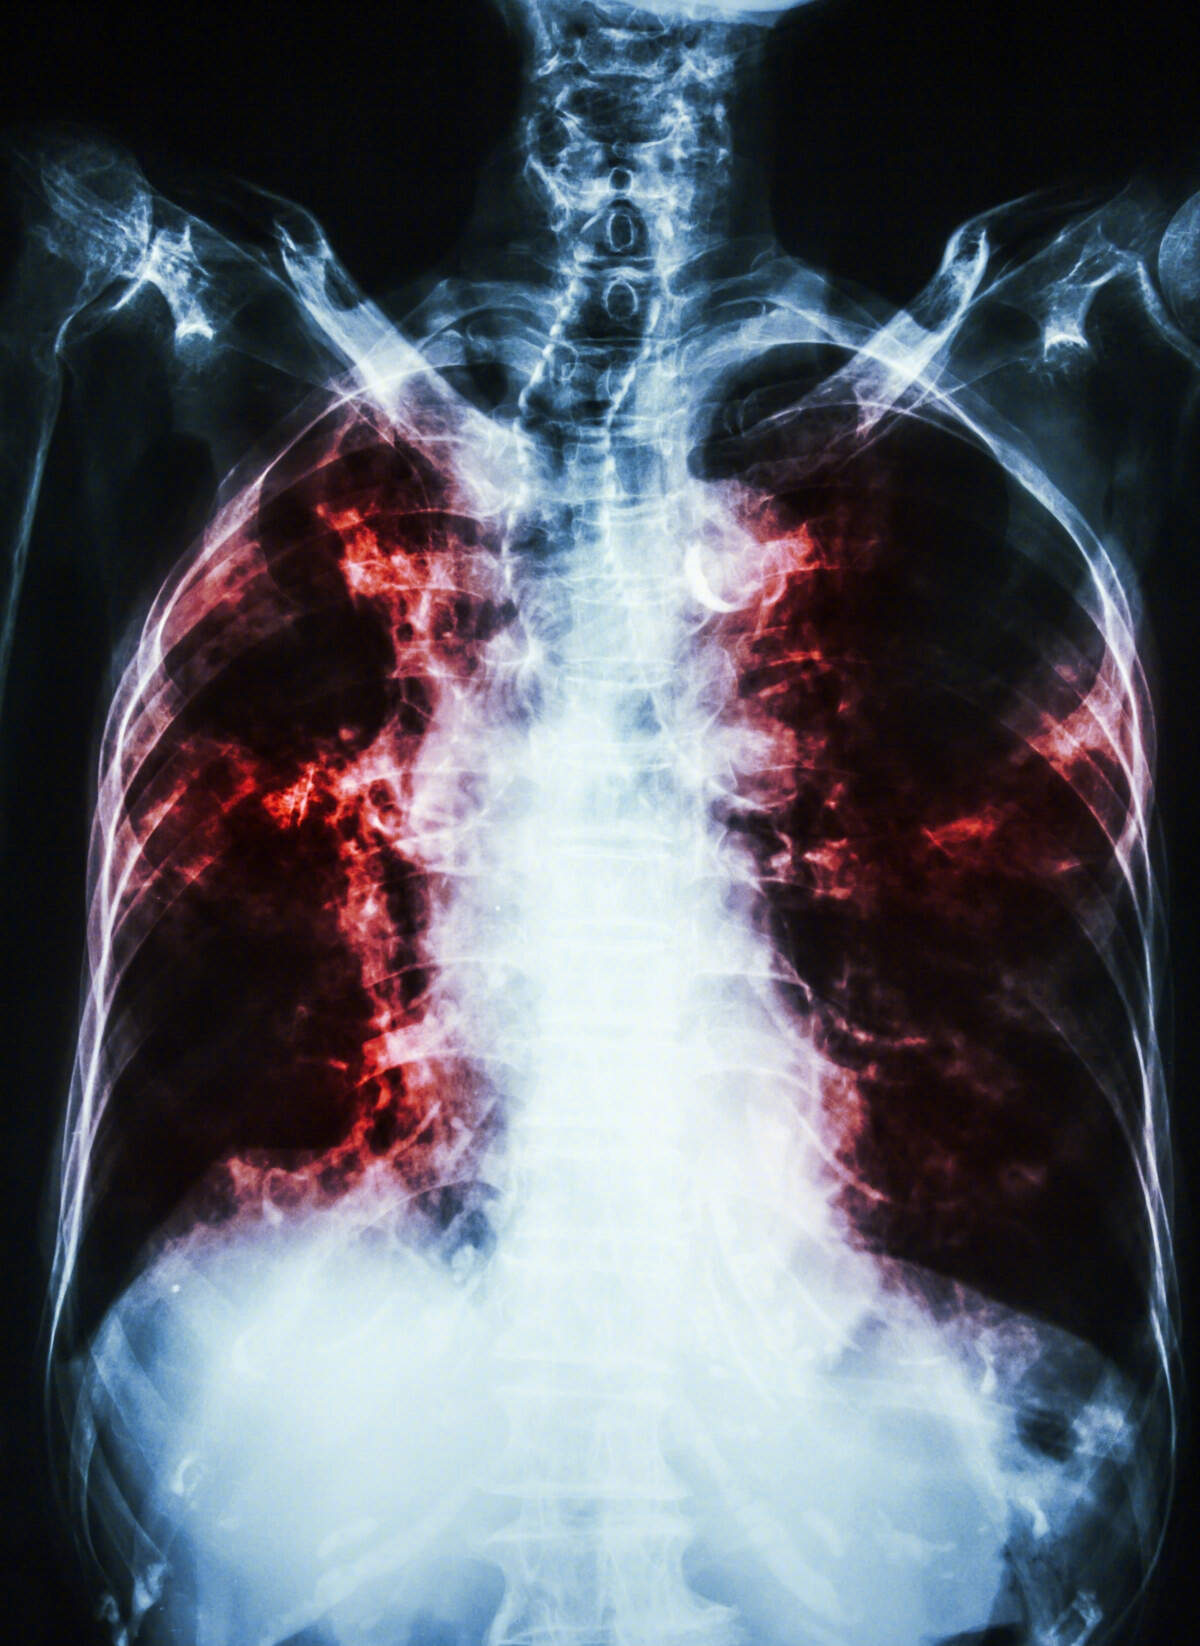

左下肺肺纤维化影像图片 有来医生